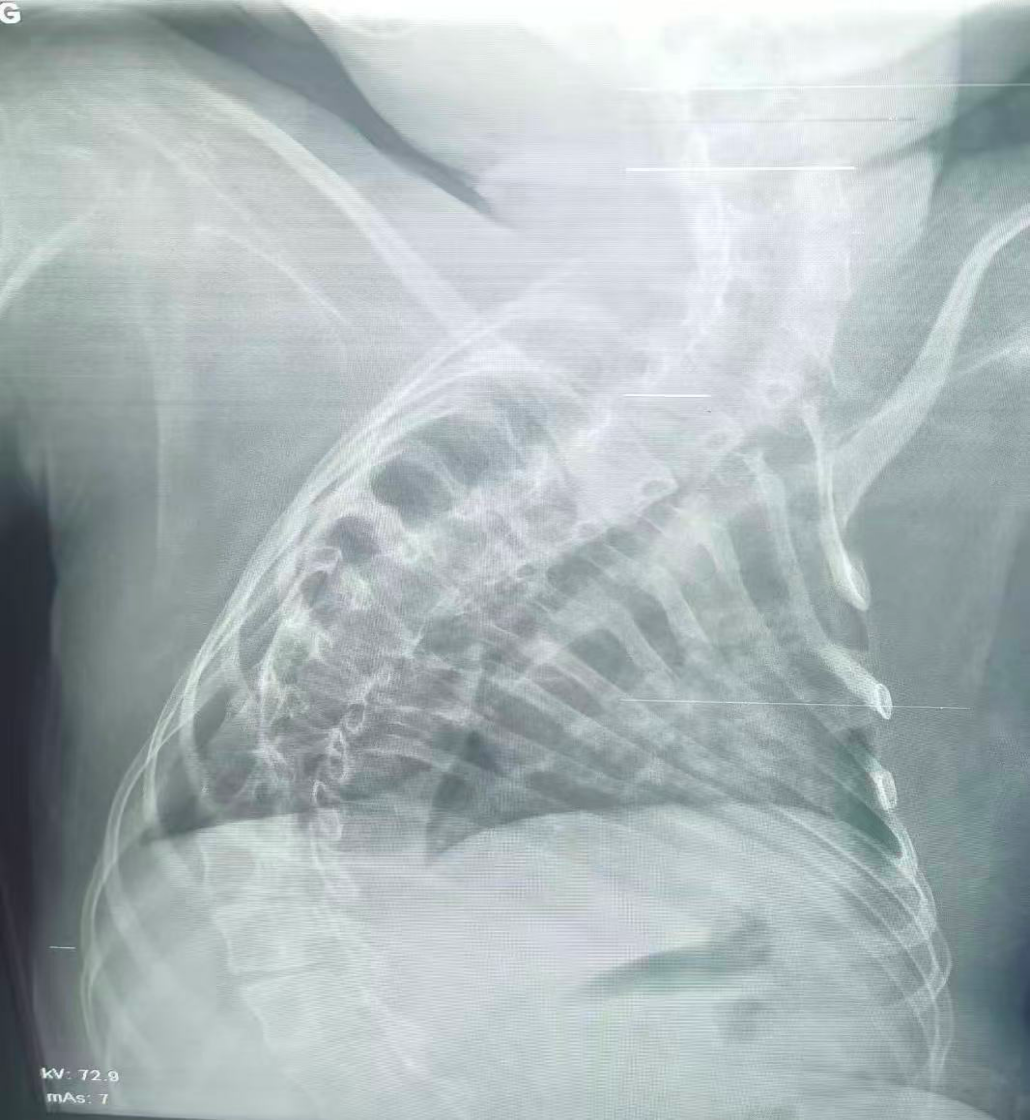

治療后

為應(yīng)對重重危機(jī),兒科團(tuán)隊制定詳盡的手術(shù)預(yù)案。手術(shù)當(dāng)日,兒科團(tuán)隊在高清內(nèi)鏡視野下,小心翼翼地操控器械避開扭曲的氣道結(jié)構(gòu),精準(zhǔn)抵達(dá)病變部位,輕柔完成灌洗、吸痰等一系列操作。

經(jīng)過團(tuán)隊的不懈努力,手術(shù)最終順利完成。術(shù)后患兒生命體征趨于平穩(wěn),氣道堵塞情況得到顯著改善,目前正在進(jìn)一步康復(fù)中。